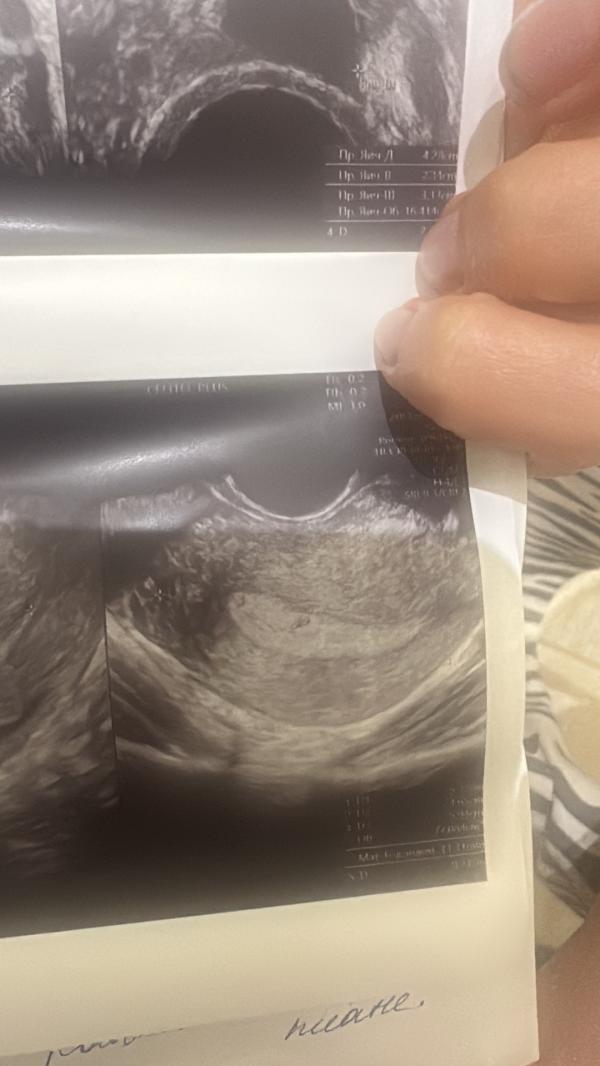

50/50 беременность сказала врач УЗИ . Сдам завтра хгч , но она сказала что как будто это плодное яйцо

@ayka.akusherka, ну само плодное яйцо под вопросом тоже , она поэтому направила на хгч

Ну она сказала что так бывает тоже , что оч маленький срок но оч похож